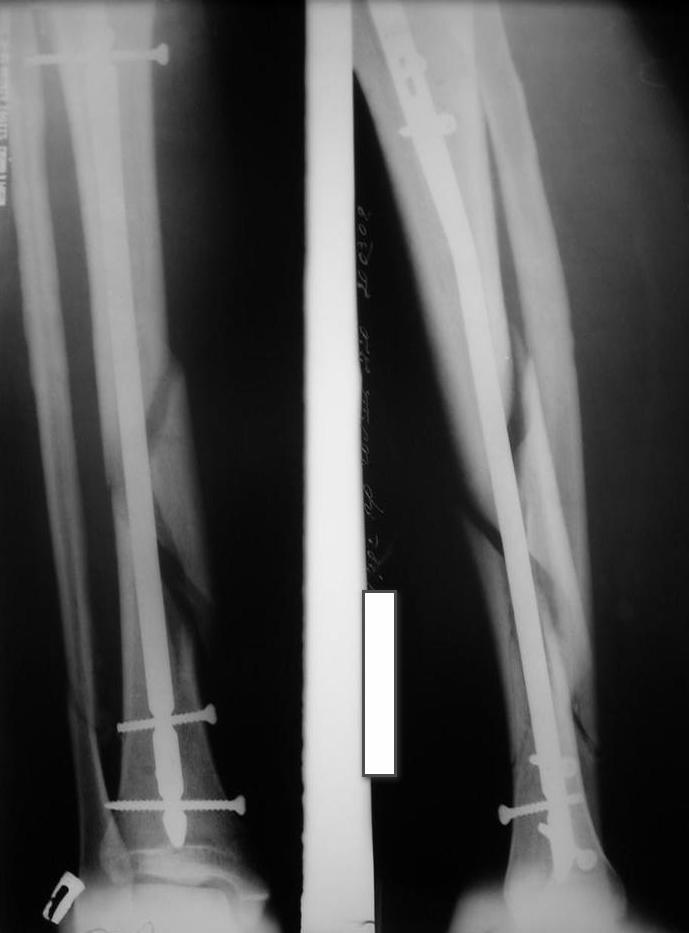

Уважаемые коллеги травматологи подскажите как нам быть и что делать. Думали всем

отделением.Несрощение оскольчатого перелома костей голени после интрамедуллярного

блокируемого синтеза.

операции пациент ходил с полной нагрузкой. Через 3 месяца на контрольных рентгенограммах

сращения нет, динамизации не выполняли, так как оскольчатый перелом.(снимки в динамике

прилагаются). Посоветуйте, что в данном случае делать наиболее целесообразно?